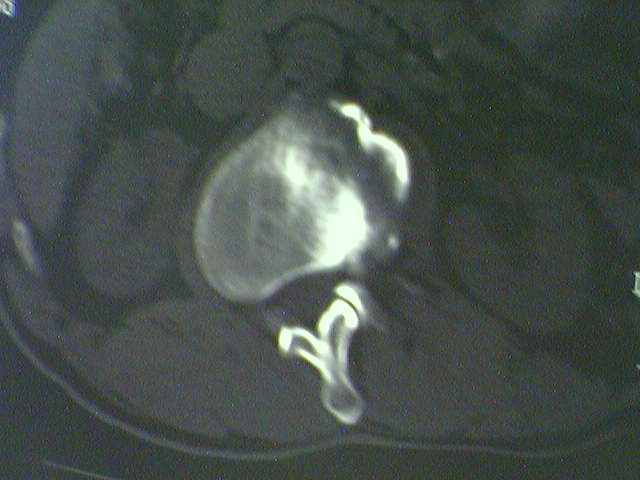

标题: CT15569:男,45岁.腰痛多年,平片腰椎明显侧弯, [打印本页]

标题: CT15569:男,45岁.腰痛多年,平片腰椎明显侧弯,

侧弯退变

侧弯,退变.